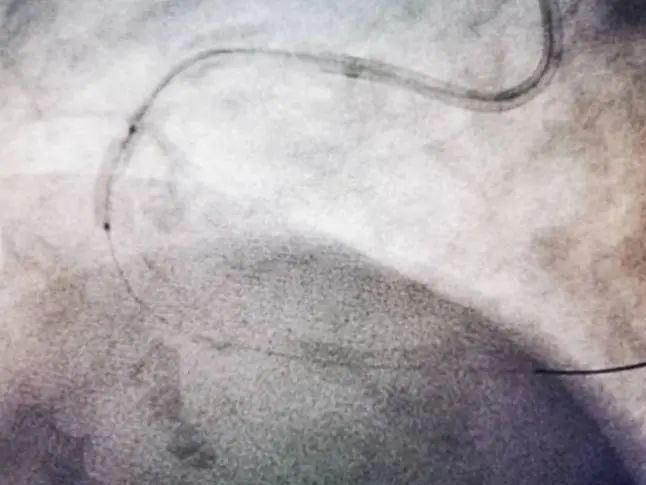

患者张女士,70岁,主因发作性剑突下疼痛6小时入院。入院诊断:冠状动脉性心脏病 急性下壁ST段抬高型心肌梗死。冠脉造影显示冠脉右冠中段钙化,且近段可见明显钙化影。孙彦博教授团队应用冠脉腔内影像学技术OCT对该血管进行了进一步的评估,结果显示:右冠中段可见360°环形钙化,此种情况极易造成支架膨胀不全。据此选择3.0×12mm Shockwave IVL冲击波球囊对中段钙化病变进行3个周期的预处理,应用OCT进一步评估显示严重钙化处出现钙化断裂,此种情况预示支架植入后可以获得满意的支架膨胀效果。果然,根据支架后OCT结果显示右冠中段严重钙化病变处支架膨胀率达108%,达到了理想的支架膨胀结果。

患者冠脉造影图像及OCT显示360°环形钙化